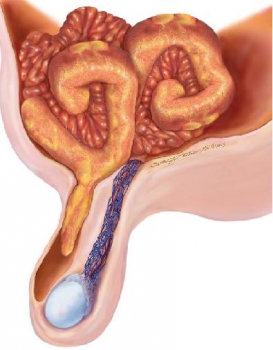

3.Thoát vị túi thừa Meckel.

Với đầu tận tự do và dài nên túi thừa Meckel có thể thoát vị vào bất cứ vị trí nào trong ổ bụng. Khoảng 50% thoát vị vào ống bẹn, 20% thoát vị đùi, 20% thoát vị rốn, và 10% thoát vị ở vị trí khác2.

Hình 19: Hình vẽ mô tả túi thừa Meckel thoát vị vào ống bẹn (Littre hernia).

(Angela D. Levy, Christine M. Hobbs (2004). Meckel Diverticulum: Radiologic Features with Pathologic Correlation. RadioGraphics 24:569)

Một trường hợp thoát vị túi thừa Meckel và ruột thừa viêm vào ống đùi.

(thoát vị De Garengeot: thoát vị ruột thừa vào ống đùi. Thoát vị Littre: thoát vị túi thừa Meckel vào ống bẹn).